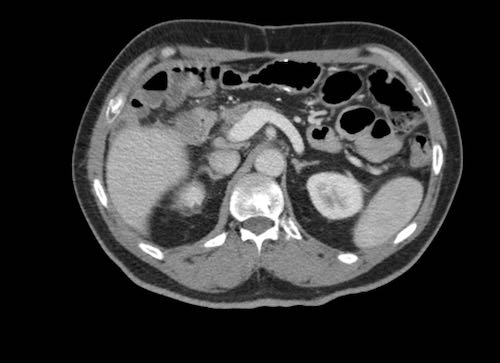

Ca lâm sàng 2

Cuộn qua các lát cắt.

Bạn có thể phát hiện tất cả các tổn thương cấy ghép phúc mạc không?

.jpeg)